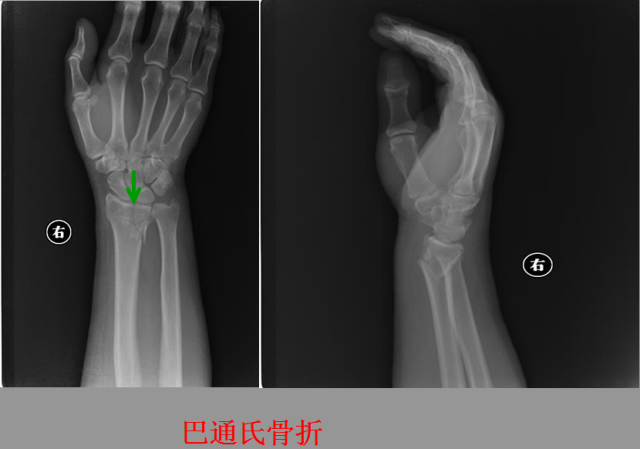

骨折篇

定义:骨折{Fracture}是指骨的完整性和连续性的折裂或粉碎。包括创伤性骨折、疲劳性骨折和病例理性骨折。 临床上以创伤性骨折*常见。